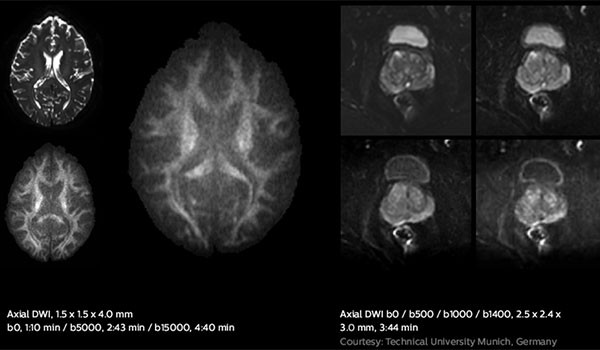

The Ingenia MR-RT has full diagnostic capabilities to confidently tackle your complex radiotherapy imaging challenges. Advanced imaging techniques, such is distortion free diffusion with DWI XD TSE, robust-motion free imaging with 3D Vane and metal artefact reduction with O-MAR, help to refine your patient-centric planning tactics. - Support to excel

The Ingenia MR-RT has full diagnostic capabilities to confidently tackle your complex radiotherapy imaging challenges. Advanced imaging techniques, such is distortion free diffusion with DWI XD TSE, robust-motion free imaging with 3D Vane and metal artefact reduction with O-MAR, help to refine your patient-centric planning tactics. - Support to excel

Fast diffusion scans

Elition 3.0T new high-performance gradients enable fast diffusion scans with high SNR, relevant for tissue characterization and treatment response monitoring.